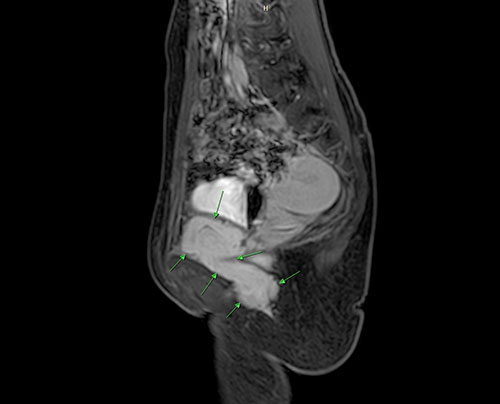

来自揭阳的陈女士(化名)今年5月突发右侧腰腹部疼痛,外院检查发现右下腹肿物,绕过耻骨联合至右外阴及肛门周围皮下,性质不明。经穿刺活检确诊为梭形细胞肿瘤,考虑肌源性或肌纤维母细胞源性肿瘤。由于肿瘤位于膀胱、直肠和阴道下段右侧,贯穿盆底,解剖位置复杂。陈女士辗转省内多家三甲医院均被告知只能进行风险极高的开放手术,且可能面临膀胱切除、输尿管损伤、子宫不保等严重后果。陈女士辗转多家医院多个科室,不仅带来了重复诊查的疲惫,更是心理上的沉重打击。面对可能的功能丧失和手术风险,陈女士几乎陷入绝望,甚至萌生放弃治疗的念头。

盆腔肿物MR图